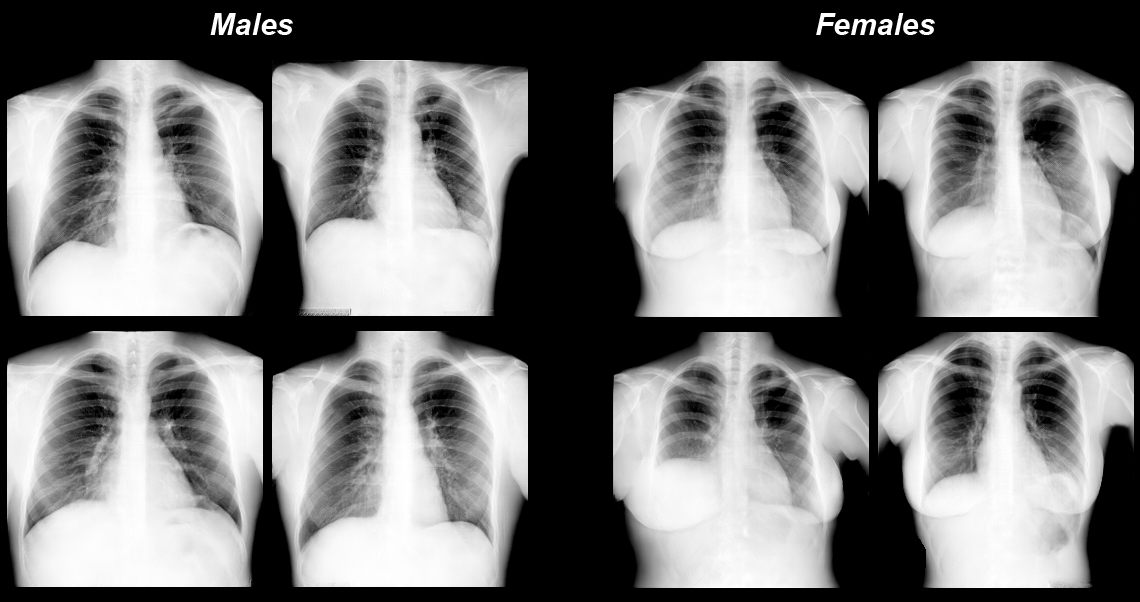

These large collections, even when completely depersonalised, are still questionable from an ethical and a security standpoint. But Kovalev and his team developed a solution. They came up with a method using Generative Adversarial Networks to automatically generate medical images, which could be used as a substitute for real ones.

Once the high visual quality and adequate quantitative properties of the artificial images were achieved, they could be used for both the training of Deep Learning models, but also for educational and illustrative purposes to assure software quality. “Using this case,” continues Dr Kovalev, “scientists would be free to do any kind of research based on such artificial data.”

So far so good. But the image generation research was based on very large private medical image databases with restricted access. These included a chest X-Ray database containing about 2,000,000 natively digital images, a database of 3D computed tomography images of 10,000 patients, and a database of histology images used for cancer diagnoses. Some slides were several Terabytes in size.